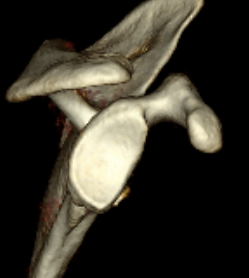

Measurement Hill Sachs

Best fit circle of the articular surface of humeral head

Measure percentage involvement of articular surface